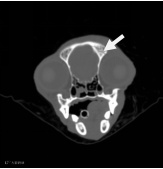

| 右侧眼眶壁内前侧骨折 |

| 右侧顶骨及颞骨骨折 |

| 大脑右侧顶部脑挫裂伤 |

| 先天性脑囟门未闭合;右侧耳道少许积液 |

1、右侧眼眶壁骨折

2、右侧顶骨及颞骨骨折伴周围软组织稍肿胀

3、大脑右侧顶部脑挫裂伤

4、先天性脑囟门未闭合

5、右侧耳道少许积液

余未见明显异常,请结合临床。